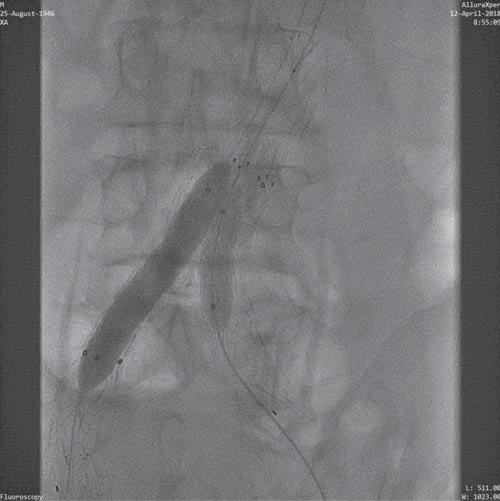

We performed a right brachial aboard with a 5F sheath, and bilateral femoral aboard: 6F sheath on the left and 8F on the right side, later changed to an 8F left, respectively 10F right, the later necessary for the introduction of the 10F Rotarex® thrombectomy catheter. The arterial punction of the right femoral artery was performed under anatomic and fluoroscopic guidance. We succeeded the crossing of the right stenosis in retrograde approach, with a hydrophilic stiff guide wire, using a 5F vertebral catheter for support. Later we exchanged the guide wire with the dedicated 0.025’’ guide wire of the Rotarex® thrombectomy system, over which we started to cross the intraprosthetic thrombus in the right extension with the 10F thrombectomy catheter. Upon penetration into the iliac segment/ right limb of the endoprosthesis the progression became strenuous, caused by the severe kinking and probably by the obstacle created by the perimeter folding at this level. Forcing the progression we were faced with the fracture of the 0.025’’ guide wire (Figure 7). Using a snare type recovery device introduced through the left femoral sheath we successfully extracted the broken guide wire from the descending aorta. We decided to continue the thrombectomy procedure using a new guide wire placed in the abdominal aorta, after a predilation with a Chronus Advanced 4/80 mm Rontis® (Rontis Medical) balloon in the area of maximum stenosis where the guide wire fracture was recorded, in order to reduce the risk of repeating the incident and to allow an easier access for the thrombectomy catheter through that area (Figure 8). Subsequently we succeeded the passage with the thrombectomy catheter and we obtained recanalization of the vascular axis from the level of the right iliac artery up to the abdominal aorta, through the endo-graft, extracting a lot of thrombus (Figure 9). We continued intervention with 8/60 mm Chronus Advanced Rontis® balloon dilatation, along the right limb and extension of the endoprosthesis and we implanted proximally inside the prosthesis right limb, a self-expandable stent Zeus® (Rontis Medical) 11/60 mm (Figure 10). Further on, we used the kissing stents technique with two balloon expandable Dynamic® (Biotronik) stents of 10/56 mm in the right limb and 10/25 mm in the left extension (Figure 11). We finally implanted another self-expandable 10/60 mm stent Protege EV3® (Medtronic) at the level of the distal right external iliac artery, forced by a flow limiting dissection area, secondary the insertion of the 10F sheath in the extremely tortuous right iliac artery (Figure 12). The final angiographic result, was considered excellent at the end of the procedure, without any flow limiting areas of stenosis and with excellent distal blood flow (Figure 13).

Figure 9. Thrombectomy passage through the entire occlusion area of the prosthesis.

Figure 10. Post-deployment self-expanding stent right limb of the prosthesis.